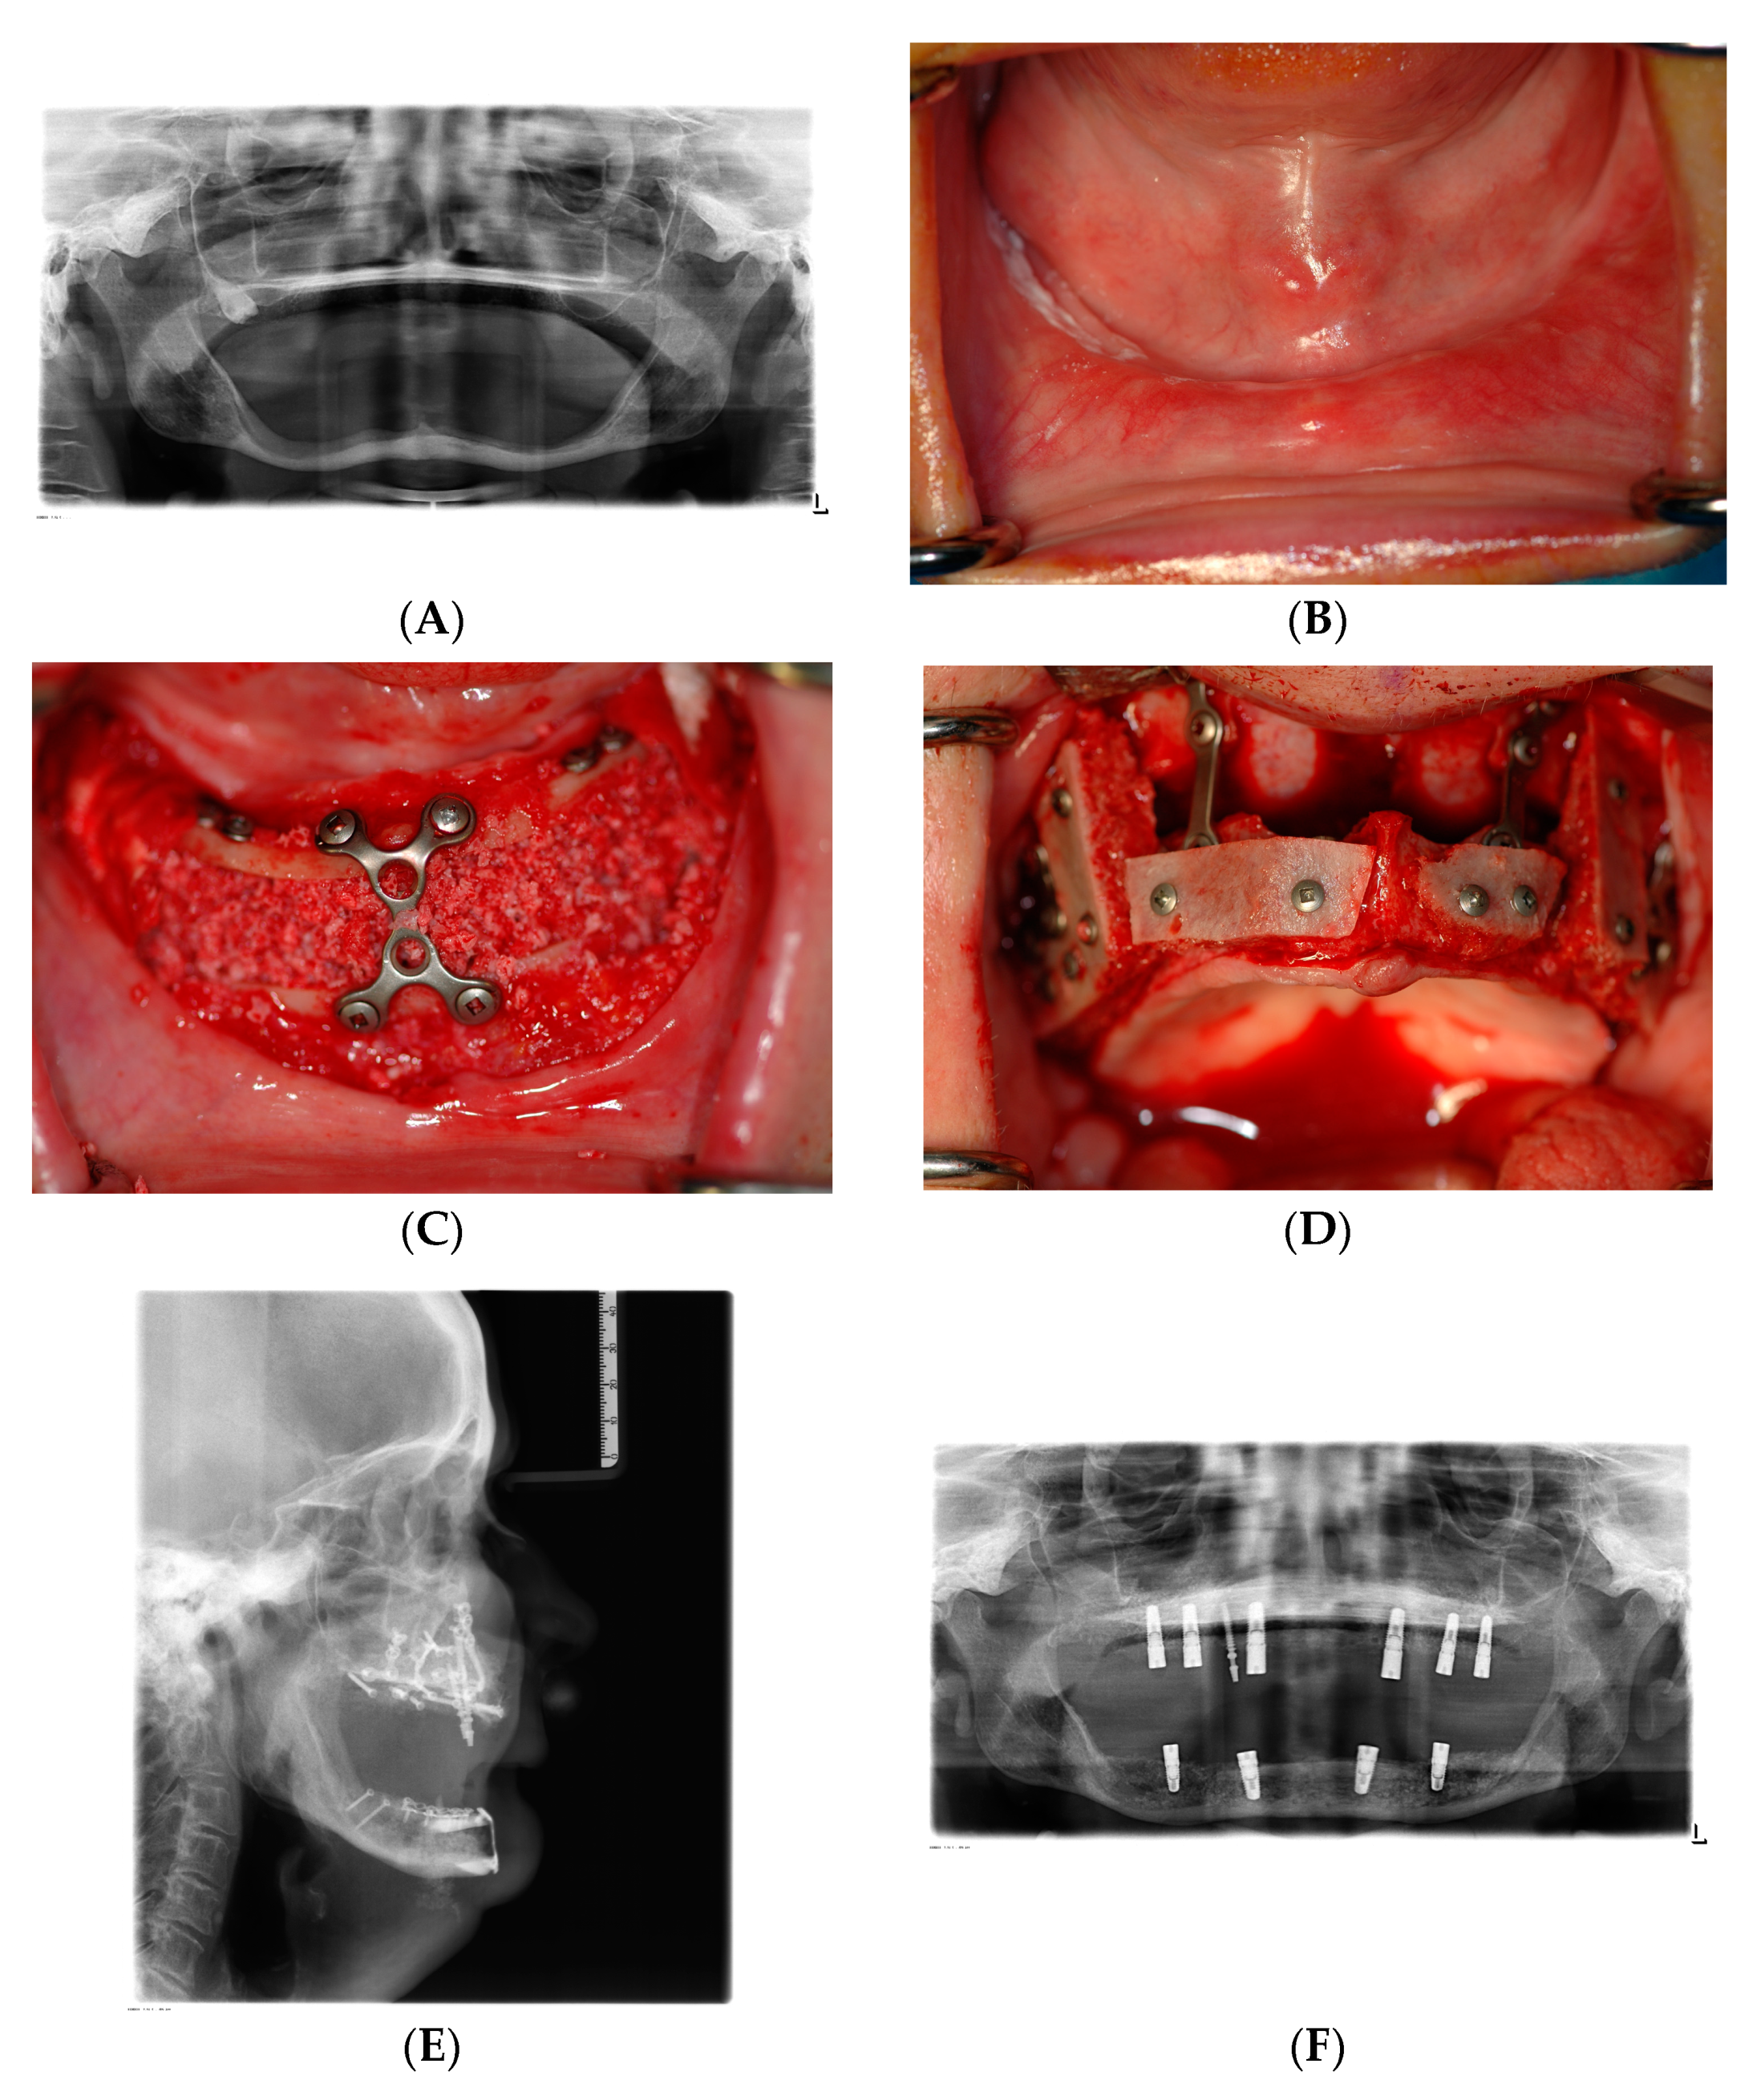

5. Vertical Ridge Augmentation—Sandwich versus Onlay Grafting